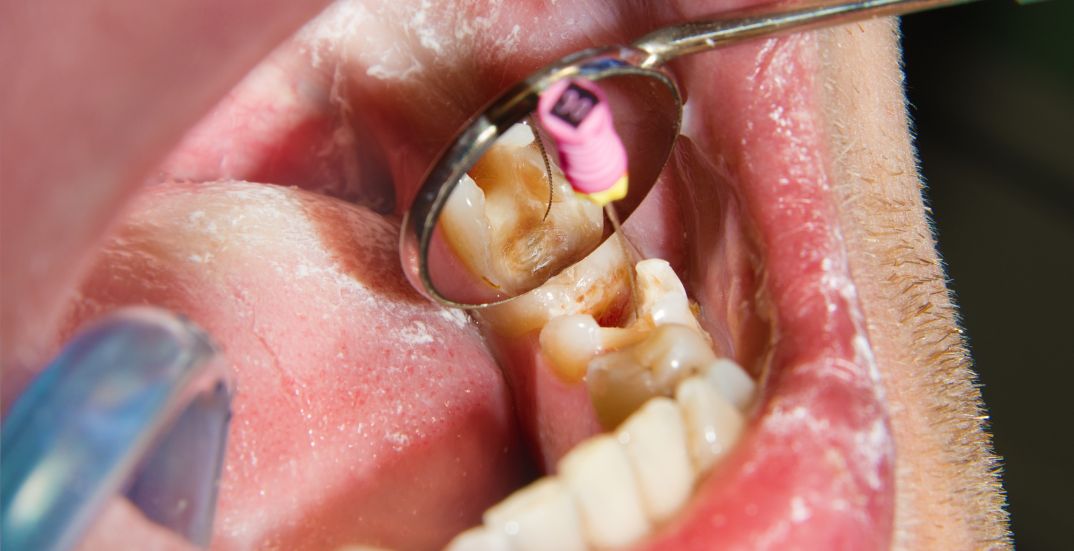

A root canal is a dental procedure that treats infection at the center of a tooth (the pulp). It’s commonly used to save a tooth that might otherwise need to be removed.

The procedure involves removing the infected pulp, cleaning and disinfecting the canal, and sealing it with a filling or crown. This helps stop the spread of infection and preserves the natural tooth structure.

The process begins with an X-ray to assess the extent of infection. The area is numbed using a local anesthetic. A small hole is made to access the pulp, which is then carefully removed. The canals are cleaned, shaped, and disinfected before being sealed. In many cases, a crown is placed later to protect the tooth.

If you have a deep cavity, a cracked tooth, or trauma to the mouth, a root canal may be recommended. Common symptoms include persistent pain, sensitivity to hot or cold temperatures, swollen gums, or discoloration of the tooth.